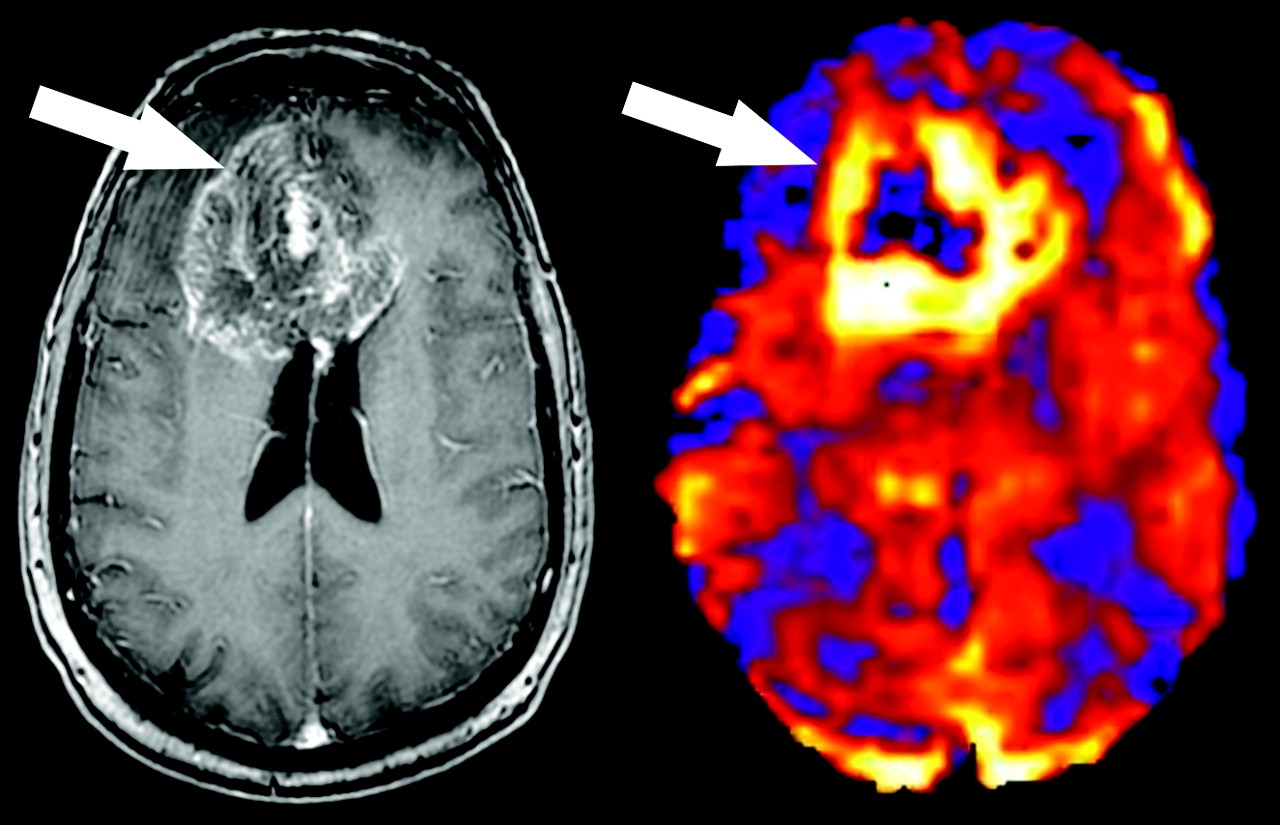

A 57-year-old woman with atypical meningioma. An avidly enhancing falcine-based mass is demonstrated on the postgadolinium image (left). ASL map demonstrates ringlike hyperperfusion corresponding to the outer margins of the tumor (right, arrow).

Hyperperfusion of a glioblastoma multiforme. Axial postgadolinium T1-weighted image demonstrates avid enhancement of a high-grade neoplasm centered in the genu of the corpus callosum. ASL CBF map demonstrates high signal intensity corresponding to increased flow within the periphery of the tumor (arrow).